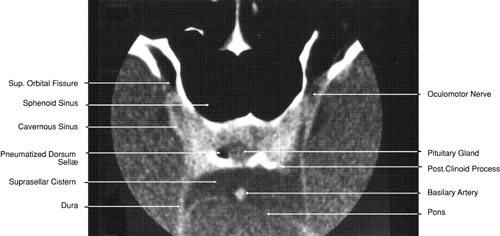

Fig. 28. Axial computed tomography image with contrast medium through cavernous sinus and pituitary gland.

Fig. 29. A. Axial computed tomography soft tissue image at the level of the base of skull. B. Axial computed tomography bone window image at the level of the base of skull.

Fig. 30. A. Axial T1-weighted image at the level of floor of orbit and trigeminal nerve. B. Axial T1-weighted image at the level of oculomotor nerve.

Fig. 31. Axial T1-weighted image through the cerebral peduncle at the level of oculomotor nerve.

Fig. 32. A. Axial computed tomography soft tissue image at the level of suprasellar cistern. B. Axial computed tomography soft tissue image at the level of thalamus. C. Axial T1-weighted image at the level of thalamus.